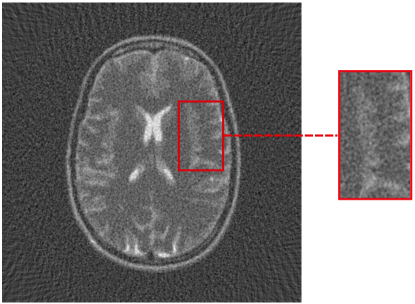

5 Benchmark procedure

To assess the performance of the HLSF, four phantoms with structural patterns of different complexity have been considered (Fig. 4). PH-1 in Fig. 4(a) is the segmentation of a reconstructed slice of mouse lung tissue at micrometer scale. PH-2 in Fig. 4(b) is a multilevel segmentation of a MRI scan of a human brain. PH-3 in Fig. 4(c) is a multilevel segmentation of a CT slice of a human lung. PH-4 is the well-known Shepp-Logan phantom [16].

Refer to caption

(b) PH-2

Figure 4: Set of simulated data used to benchmark the HLSF. PH-1 has 784 ×\times 784 pixels; PH-2 has 592 ×\times 592 pixels; PH-3 has 500 ×\times 500 pixels; PH-4 has 512 ×\times 512 pixels.